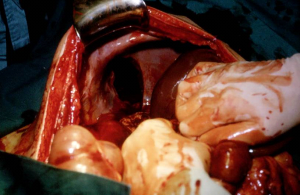

הטיפול בקרעים בסרעפת הוא כירורגי. הגישה היא בדרך כלל בטנית, עקב השיעור הגבוה של חבלות בטניות נלוות בפציעות מסוג זה. רוב הקרעים מתרחשים בצד השמאלי של הסרעפת, מכיוון שבצד הימני הכבד מגן על הסרעפת בפני חבלה קהה. לאחר פתיחת הבטן וזיהוי הקרע תופרים את הסרעפת בתפרים שאינם נספגים (תמונות).

| תמונה 5.16: קרע בסרעפת ותפירתה. עליון ימין רואים את הקרע, עליון משמאל חשיפת הקרע. תחתון תפירת הקרע | |